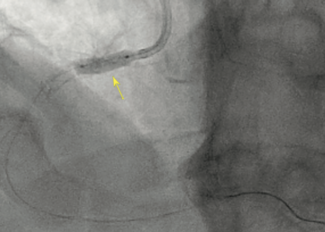

An 80-year-old man with a history of acute inferior myocardial infarction was admitted to our hospital. He had undergone bare-metal stent (3.5/28 mm) implantation in the mid-right coronary artery 22 years prior.